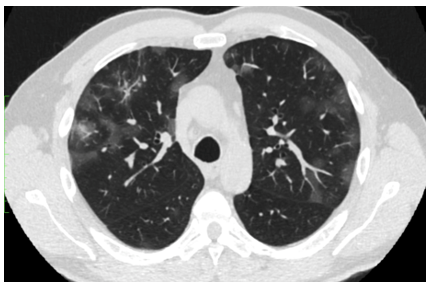

· Tomografía axial computarizada de tórax que reflejó infiltrado algodonoso bilateral con distribución parchada, además de infiltrados periféricos y subpleurales (figura 1).

Figura 1. Tac de tórax